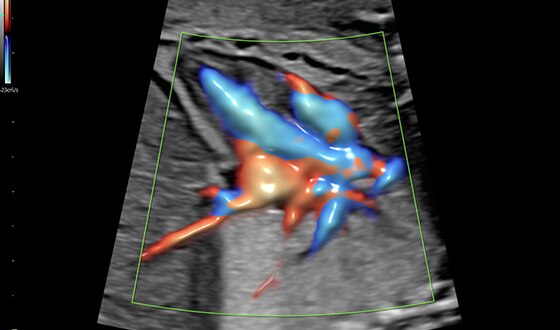

15-week fetal circulatory system with eSTIC and HD-Flow™